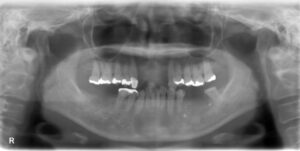

上下14本欠損症例

BEFORE AFTER 73歳女性/上下14本欠損/インプラント埋込手術 【治療内容】 今まで義歯を使用されていました…